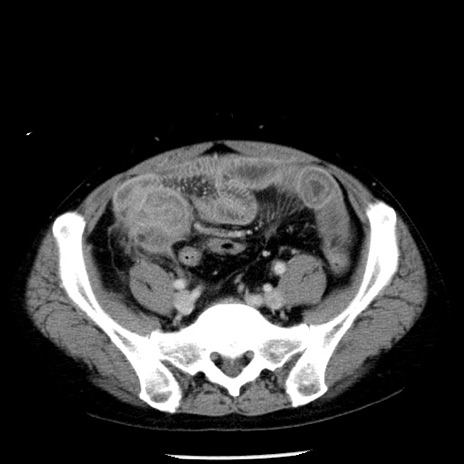

症例29(横断像)

【症例】40歳代男性

【現病歴】2日前から胃痛あり。徐々に周期的な激痛に変化した。本日になっても激痛があるため受診。

【身体所見】意識清明、BT 38-39℃台あり、腹部:膨満、やや硬、右下腹部に圧痛あり。

【データ】WBC 8500、CRP 23.26